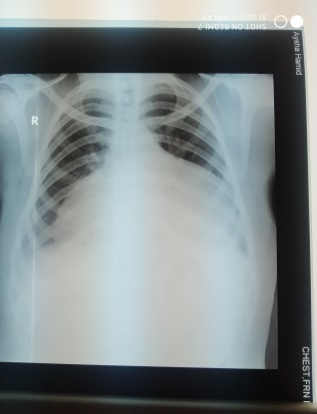

A 40year old female presented to the emergency unit at Atabra teaching hospital river nilestate, Sudan. Complaining of exertionaldysponea and lower limb swelling for one week. She has no orthopnea, paroxysmal nocturnal dysponea, chest pain or cough. The patient also reported symptoms of hypothyroidism for the last month in form of weight gain despite decreased appetite, fatigue, hair loss, muscle and joint pain and irregular cycle. She was not known to have any chronic illnesses before. On examination patient was ill, clinically anemic, PR88lmin RR20lmin and BP 110/80. There were features of hypothyroidism in the form of per orbital edema, muffled heart sound with normal respiratory sound. No murmur, gallop rhythm orengorgement of the jugular veins. Chest X-ray (Figure 1) showed increased cardiothoracic ratio. Ejection fraction at echocardiography was 66%, due to detection of pericardial fluid levels of 2.2 anteriorly and 3-4 posteriorly, a diagnosis of massive pericardial effusion was made.

Figure 1 Chest X-ray showed increased cardiothoracic ratio.